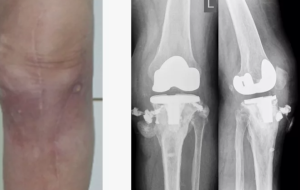

Остеомиелит — тяжелое инфекционно-воспалительное заболевание костной ткани, вызываемое преимущественно бактериальными возбудителями, такими как Staphylococcus aureus, Pseudomonas aeruginosa, и другими патогенами [1–4]. Несмотря на достижения современной антимикробной терапии, лечение пациентов с остеомиелитом остается сложной задачей из-за формирования биоплёнок, устойчивости к антибиотикам и хронизации воспалительного процесса [5–7].

Объект исследования — клинически значимые штаммы бактерий K. pneumoniae (n = 12), P. aeruginosa (n = 12), S. aureus (n = 12), S. epidermidis (n = 12), выделенные из ран пациентов c хроническим остеомиелитом.